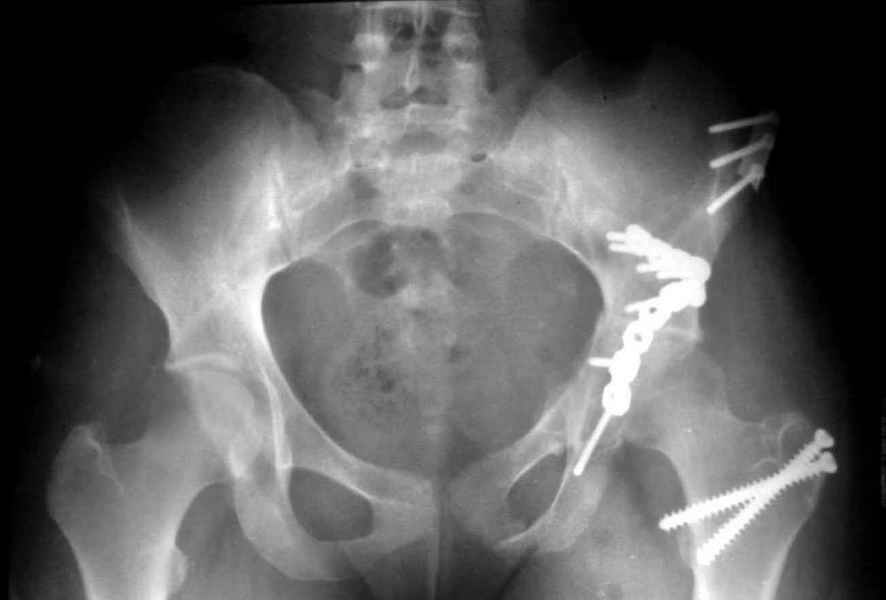

Посылаю схемы и 3D реконструкцию подобного повреждения. Называется он полным высоким двухколонным переломом вертлужной впадины, а "переломы крыла и тела подвздошной кости" входят в это понятие.

1 закрытая репозиция аппаратом + фиксация через проколы винтами

2 закрытая репозиция передней колонны + открытая задней колонны из задне-неружного доступа

3 открытая репозиция передней колонны из подвздошнго доступа + открытая задней колонны из задне-наружного доступа

4 открытая репозиция из илиоингвинального доступа

5 открытая репозиция из Y образного доступа

Я бы ориентировался на Y образный доступ

или из двух если есть сомнения в целостности задних отделов крыла.

прикладываю схему доступа и случай.

Одним задне наружным переднюю колонну не достать, а илио-ингвинальный более сложный не позволяет контролировать суставную поверхность и трудно управлять задней колонной.